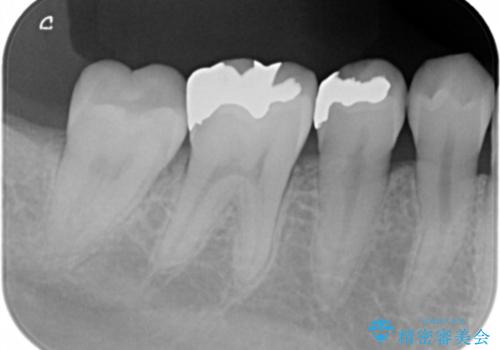

銀の詰め物を外し、拡大鏡で虫歯がないか確認してe-maxインレーで治療をしました。

- e-maxインレー 7.7万円 費用は治療当時の料金となります

- 天然歯を削ります

- 硬い素材は天然歯を傷つけてしまう場合があります

- かみ合わせや歯ぎしりが強すぎる方はセラミックが割れてしまう可能性があります